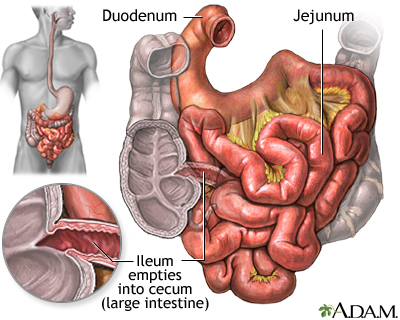

An upper GI and small bowel series is a set of x-rays taken to examine the esophagus, stomach, and small intestine.

An x-ray method called fluoroscopy tracks how the barium moves through your esophagus, stomach, and small intestine. Pictures are taken while you sit or stand in different positions.

Abnormal results in the small intestine may indicate the following problems:

- Diverticulosis

- Malabsorption syndrome

- Narrowing (stricture)

- Swelling and irritation (inflammation) of the small intestines

- Tumors

- Ulcers